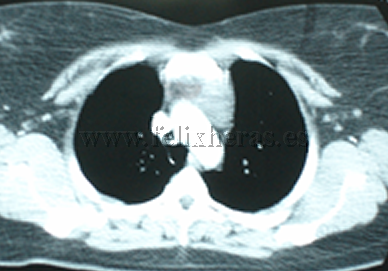

Timoma |

Seminoma |